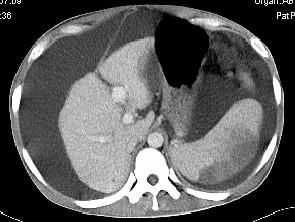

问题 患者男,29岁,乙肝病史10余年,腹胀,有移动性浊音,影像检查如图,最全面的诊断是 ( )

选项 A、大网膜膈下间位及脾梗 B、胆结石及脾梗 C、肝硬化腹水 D、肝硬化腹水、脾梗、胆囊结石 E、肝硬化

答案 D